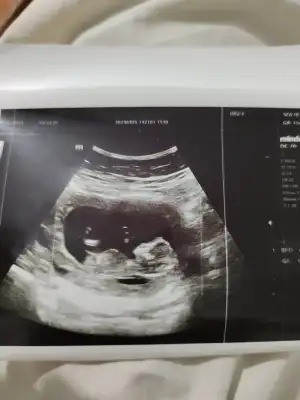

kızlar çıktım kontrolden. 12+2 tam günü gününe. Asker selamı verdi sürekli çok komikti:) nub a göre erkeğe yakın ama çok da dik değil bazen klitoris de böyle görünüyor kan testini bekleyeceğiz. Valla bi fikriniz varsa siz de bakın:)

Hem asker pozunu, hem nubun belli olduğunu atıyorum:)

Nubu yatay gibi😊 kıza daha yakın bence